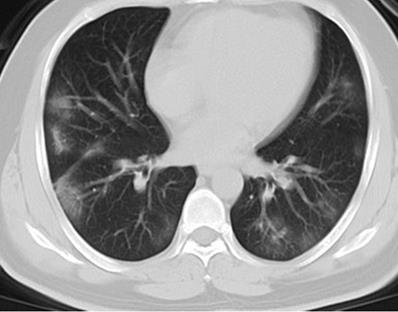

Figure 2

Initial chest CT of a 41-year-old man who presented with fever and cough for 3 days. Bilateral multiple patchy ground glass opacities (GGOs), with peripheral distribution were seen. The patient was discharged 6 days later after symptom improvement.

As shown in Table 2, all (100%) patients had abnormal CT findings at admission, 210 (94%) patients had bilateral lung involvement, and 102 (45%) patients had more than four lung zones involved. With regard to the distribution of lung lesions, 114 (51%) patients had peripheral distribution, 105 (47%) patients had both central and peripheral distribution, while only 5 (2%) patients had central distribution. Considering lung opacity, 210 (94%) patients had GGO, 46 (21%) patients had consolidation, 37 (17%) patients had GGO with consolidation, 137 (61%) patients had GGO with interstitial thickening, and 38 (17%) patients had air bronchogram (Figure 1, Figure 2). In addition, 2 (1%) patients had lymphadenopathy, and 3 (1%) patients had pleural effusion.